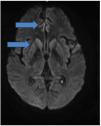

Case reportA 59-year-old man was diagnosed with HIV associated with Pulmonary Tuberculosis (TB) in late 2012 (at age 48) through ELISA and Western Blot serological tests, as well as a sputum culture for Acid-Fast Bacilli (AFB). He initially received treatment for TB, followed by Antiretroviral Therapy (ART) two weeks later, consisting of tenofovir (TDF), lamivudine (3TC), and efavirenz (EFV). Laboratory tests before starting ART showed a CD4 count of 18 cells/mcL (4 %) and a CD8 count of 203 cells/mcL (45 %), with a Viral Load (VL) of 224,906 copies/mL (Log=5.35). After completing TB treatment, his CD4 count increased to 167 cells/mcL (17.9 %), and his VL decreased to 82 copies/mL (Log=1.91). The patient developed Immune Reconstitution Inflammatory Syndrome (IRIS) with cervical lymphadenitis, which was managed with aspiration, and experienced persistent peripheral neuropathy during TB treatment, requiring pyridoxine supplementation. During this period, he also developed systemic arterial hypertension, type 2 diabetes mellitus, dyslipidemia, and keratitis related to past pterygium surgery. After 11-years of regular antiretroviral therapy, which was later switched to lamivudine and dolutegravir, he maintained persistent undetectable HIV viremia and adequate pharmacological control of systemic arterial hypertension, type 2 diabetes and hypercholesterolemia, using losartan 50 mg/day, metformin 1g/day, and atorvastatin 10 mg/day. He persistently reported bilateral 'boot distribution' paresthesia, attributed to an adverse reaction to isoniazid. During a routine follow-up on May 8, 2023, he mentioned that his partner had been complaining about him forgetting personal items, such as his wallet and car keys, despite the patient’s own disagreement. At this time the International HIV Dementia Scale scored seven points, and a brain MRI was recommended. Unfortunately, he did not undergo the requested brain MRI and returned only three months later, experiencing a sudden worsening of symptoms, including increased neuropathy, weight loss, social withdrawal, and somnolence. Neurological examination revealed temporal disorientation, ataxia, a left Babinski sign, hyperreflexia in the right patellar tendon, exhausted clonus in the right foot, and dysdiadochokinesia. Myoclonus was not present. Hospitalization was recommended, when evaluated by a neurologist, and MRI (in August 9) showed a restricted diffusion hypersignal located bilaterally in the insula, basal ganglia, and anterior cingulate cortex (Fig. 1). Seventeen days after this first and brief hospitalization, MRI showed symmetric and bilateral hypersignal in the caudate and putamen, as well as in the superior frontal gyri (Fig. 2). Concurrent laboratory tests showed no abnormalities, including a non-reactive VDRL and normal renal, thyroid, and liver function. A lumbar puncture was also performed, and partial analysis of the Cerebrospinal Fluid (CSF) revealed normal cell counts and glucose and protein levels. Tests for pyogenic bacteria, fungi, and tuberculosis and PCR for herpes simplex virus types 1 and 2 were all negative. RNA PCR for HIV in the CSF was also negative. In addition, CSF autoantibodies for autoimmune and paraneoplastic encephalitis and 14-3-3 protein analyses were requested. At this point, we suspected rapidly progressive dementia, with prion disease and immune-mediated encephalitis considered as the main possibilities. Due to the delay in obtaining the 14-3-3 protein results, the patient was hospitalized for pulse therapy with methylprednisolone (1.0 g/day for 5-days), followed by intravenous immunoglobulin (IVIG – 2.0 g/kg for 5-days). During the second hospitalization (lasted 56-days), repeat MRI showed the same abnormalities described above, but the patient’s condition worsened, with further memory decline, spastic tetraparesis, hypophonia, and bradykinesia in both the upper and lower limbs. Furthermore EEG video was performed due to its longer duration in an attempt to capture changes characteristic of CJD, such as triphasic waves. The disease progression was rapid, leading to a state of akinetic mutism. A Gastrostomy Tube (GTT) was placed due to dysphagia. The patient developed a fever caused by aspiration pneumonia, which was treated with antibiotics, and was discharged with the GTT, spastic tetraparesis and akinetic mutism. After 60-days, the 14-3-3 protein results were received, revealing high titers, and the family was consulted about initiating palliative care to avoid invasive measures. During his course, the patient underwent 3 EEGs, all of which revealed only nonspecific slowing. RT-QuIC analysis of the CSF was positive. He passed away 6-months after the onset of neurological symptoms.

Alongside the clinical presentation, complementary examinations play a key role in the diagnosis of CJD3,13. Brain MRI typically reveals lesions characterized by Diffusion-Weighted Imaging (DWI) hyperintensities and signal abnormalities on FLAIR and T2-weighted sequences, particularly in the cerebral cortex and basal ganglia, as observed in the present case14 .Electroencephalogram findings, though limited in sensitivity, may show triphasic waves or periodic complexes, which can contribute to the diagnosis15. Cerebrospinal fluid analysis can help detect elevated levels of proteins such as 14-3-3, tau, and p-tau, which are associated with the disease16. Furthermore, the identification of pathological prion protein through RT-QuIC in nasal mucosa or CSF is notable for its high specificity17.